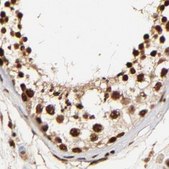

Anti-MED12 antibody produced in rabbit, a Prestige Antibody, is developed and validated by the Human Protein Atlas (HPA) project . Each antibody is tested by immunohistochemistry against hundreds of normal and disease tissues. These images can be viewed on the Human Protein Atlas (HPA) site by clicking on the Image Gallery link. The antibodies are also tested using immunofluorescence and western blotting. To view these protocols and other useful information about Prestige Antibodies and the HPA, visit sigma.com/prestige.

• IHC tissue array of 44 normal human tissues and 20 of the most common cancer type tissues.